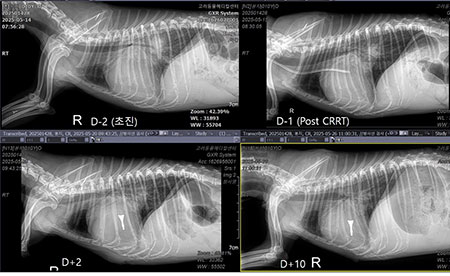

아마 이 아이에게는 모든 순간이 넘어야 하는 높은 산이었을 것이다. 멀리서 내가 할 수 있는 것은 응원 뿐. 그리고 다음날 환자의 방사선 사진이 메시지로 도착했다[그림 2, 3].

투석 만세다. 아이는 잠시 위기에서 탈출했다. 투석을 하면 신장도 위기에서 구해낼 수 있지만 폐수종도 초여과를 통해 해결할 수 있다. 이런 상황을 만들면 단 며칠 이뇨제 요구량도 감소한다.

그래서 이 아이는 어떻게 되었을까? 아이의 수술 전 방사선부터 수술 10일 차의 방사선 사진은 이렇다[그림 5, 6].

이렇게 되었다. stage D 환자에서 이뇨제를 고용량으로 쓰고, 신수치가 많이 오르고, 핍뇨나 무뇨까지 갔던 환자들에게 V-clamp 수술을 해놓으면 어떻게 될까?